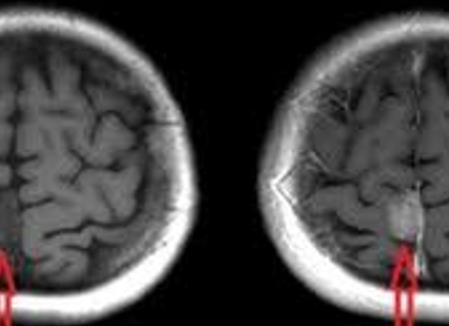

Визуализировать органы шеи и мягкие ткани очень сложно на рентгене, для этого применяются контрасты, да и то диагноз выставляют косвенно. Революционным открытием в этом направлении стало МРТ (магнитно-резонансная томография), она позволяет увидеть патологию мягких тканей. У человека в области шеи, головы есть много органов, сосудов, нервов, которые необходимо визуализировать, чтобы установить точный диагноз. Проведенное МРТ шейного отдела, головы позволяет это сделать наиболее качественно и оптимально.